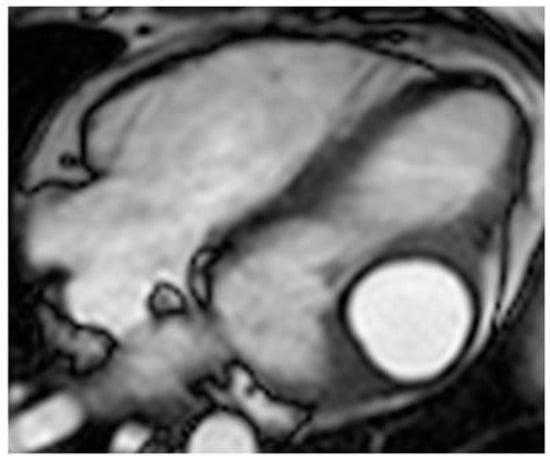

| Myxoma | Adulthood. Carney complex. | LA | Usually, asymptomatic. Rarely, intracardiac obstruction, embolic events and constitutional symptoms | Mobile mass arising from the IAS | Globular or spherical, with a friable surface and heterogeneous internal echogenicity | Heterogeneous, low attenuation, may be calcified | Isointense T1w, High T2w, heterogeneous LGE |